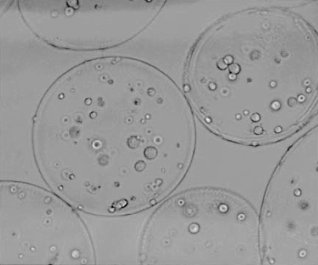

In een artikel, dat in 2003 verscheen in Endocrinology, vertellen onderzoeksleider Anthony Atala en eerste auteur Marcelle Machluf over een experiment met Leydigcellen uit de testes van ratten. Leydigcellen produceren testosteron. De onderzoekers weekten de cellen los uit de weefsels, en plakten ze vervolgens in bolletjes van het polymeer alginate-poly-L-lysine. Hieronder zie je die bolletjes onder een microscoop.